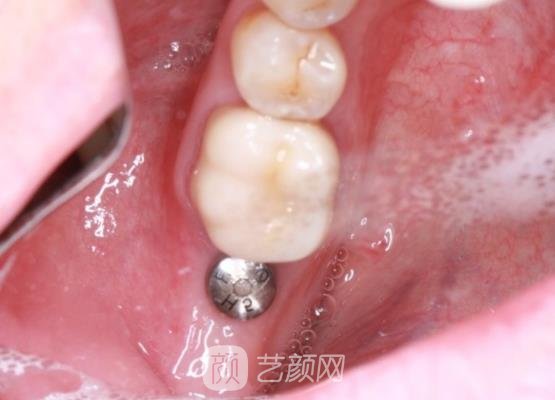

在和医生共同确定了手术的时间之后,就开始了手术的调节。调节的过程中很轻松,并没有出现什么意外的情况,而且医生也在不断的安慰我的情绪。手术的进行过程很顺利,而且完成的很快速。在做完手术之后还是有一些不适应,医生告诉我这种情况是比较正常的,让我不用担心。

手术的恢复大概用了4个多月的时间,因为我的个人体质比较好,而且在手术之后的护理工作也做得比较好,因此手术的恢复就很快速。恢复了以后的牙齿变得特别的牢固,并且也没有出现什么意外的情况,这对于我来说是再好不过的一件事了,对于这次的手术体验,我很开心。